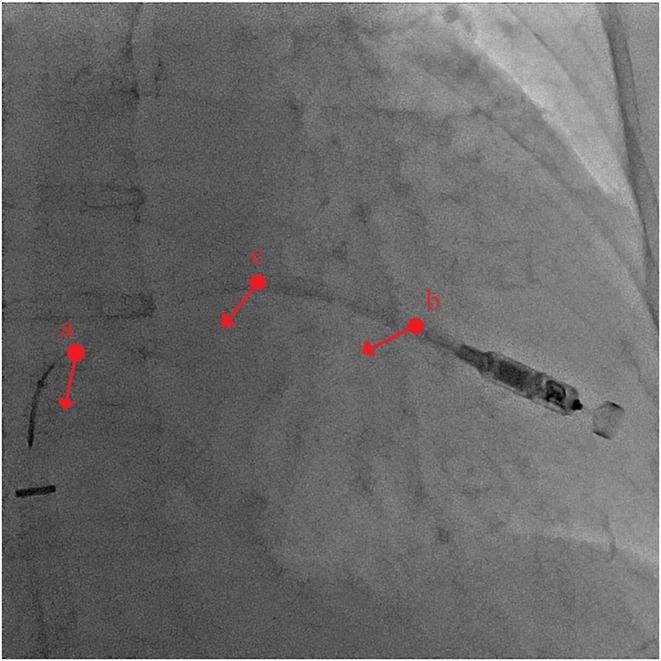

Leadless pacemaker implantation in a patient with severe right atrium dilation was unsuccessful using the conventional approach. The delivery system failed to gain sufficient backup force from the atrial wall and moved upward within the dilated atrium. To overcome this, the snare technique was employed. By securing the slightly distal portion of the top of the shaft curve, the pushing force was effectively transmitted to the tip of the system, creating a stable gooseneck shape for successful implantation.

对于一名患有严重右心房扩张的患者,采用传统方法进行无导线起搏器植入未成功。输送系统未能从心房壁获得足够的支撑力,在扩张的心房内向上移动。为克服这一问题,采用了圈套技术。通过固定轴曲线顶部稍远的部分,推力有效地传递到系统尖端,形成稳定的鹅颈形状,从而成功植入。